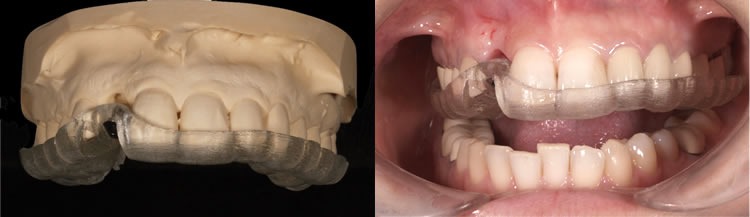

ガイデッドサージェリー